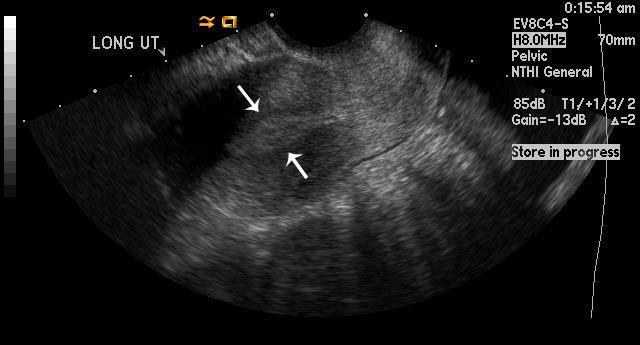

Figure 1

Uterus is empty with no gestational sac, which is concerning for ectopic pregnancy in this patient with a b-HCG level above 2000 mIU/ml. The arrows outline a central hyperechoic area that represents the normal endometrial stripe. |